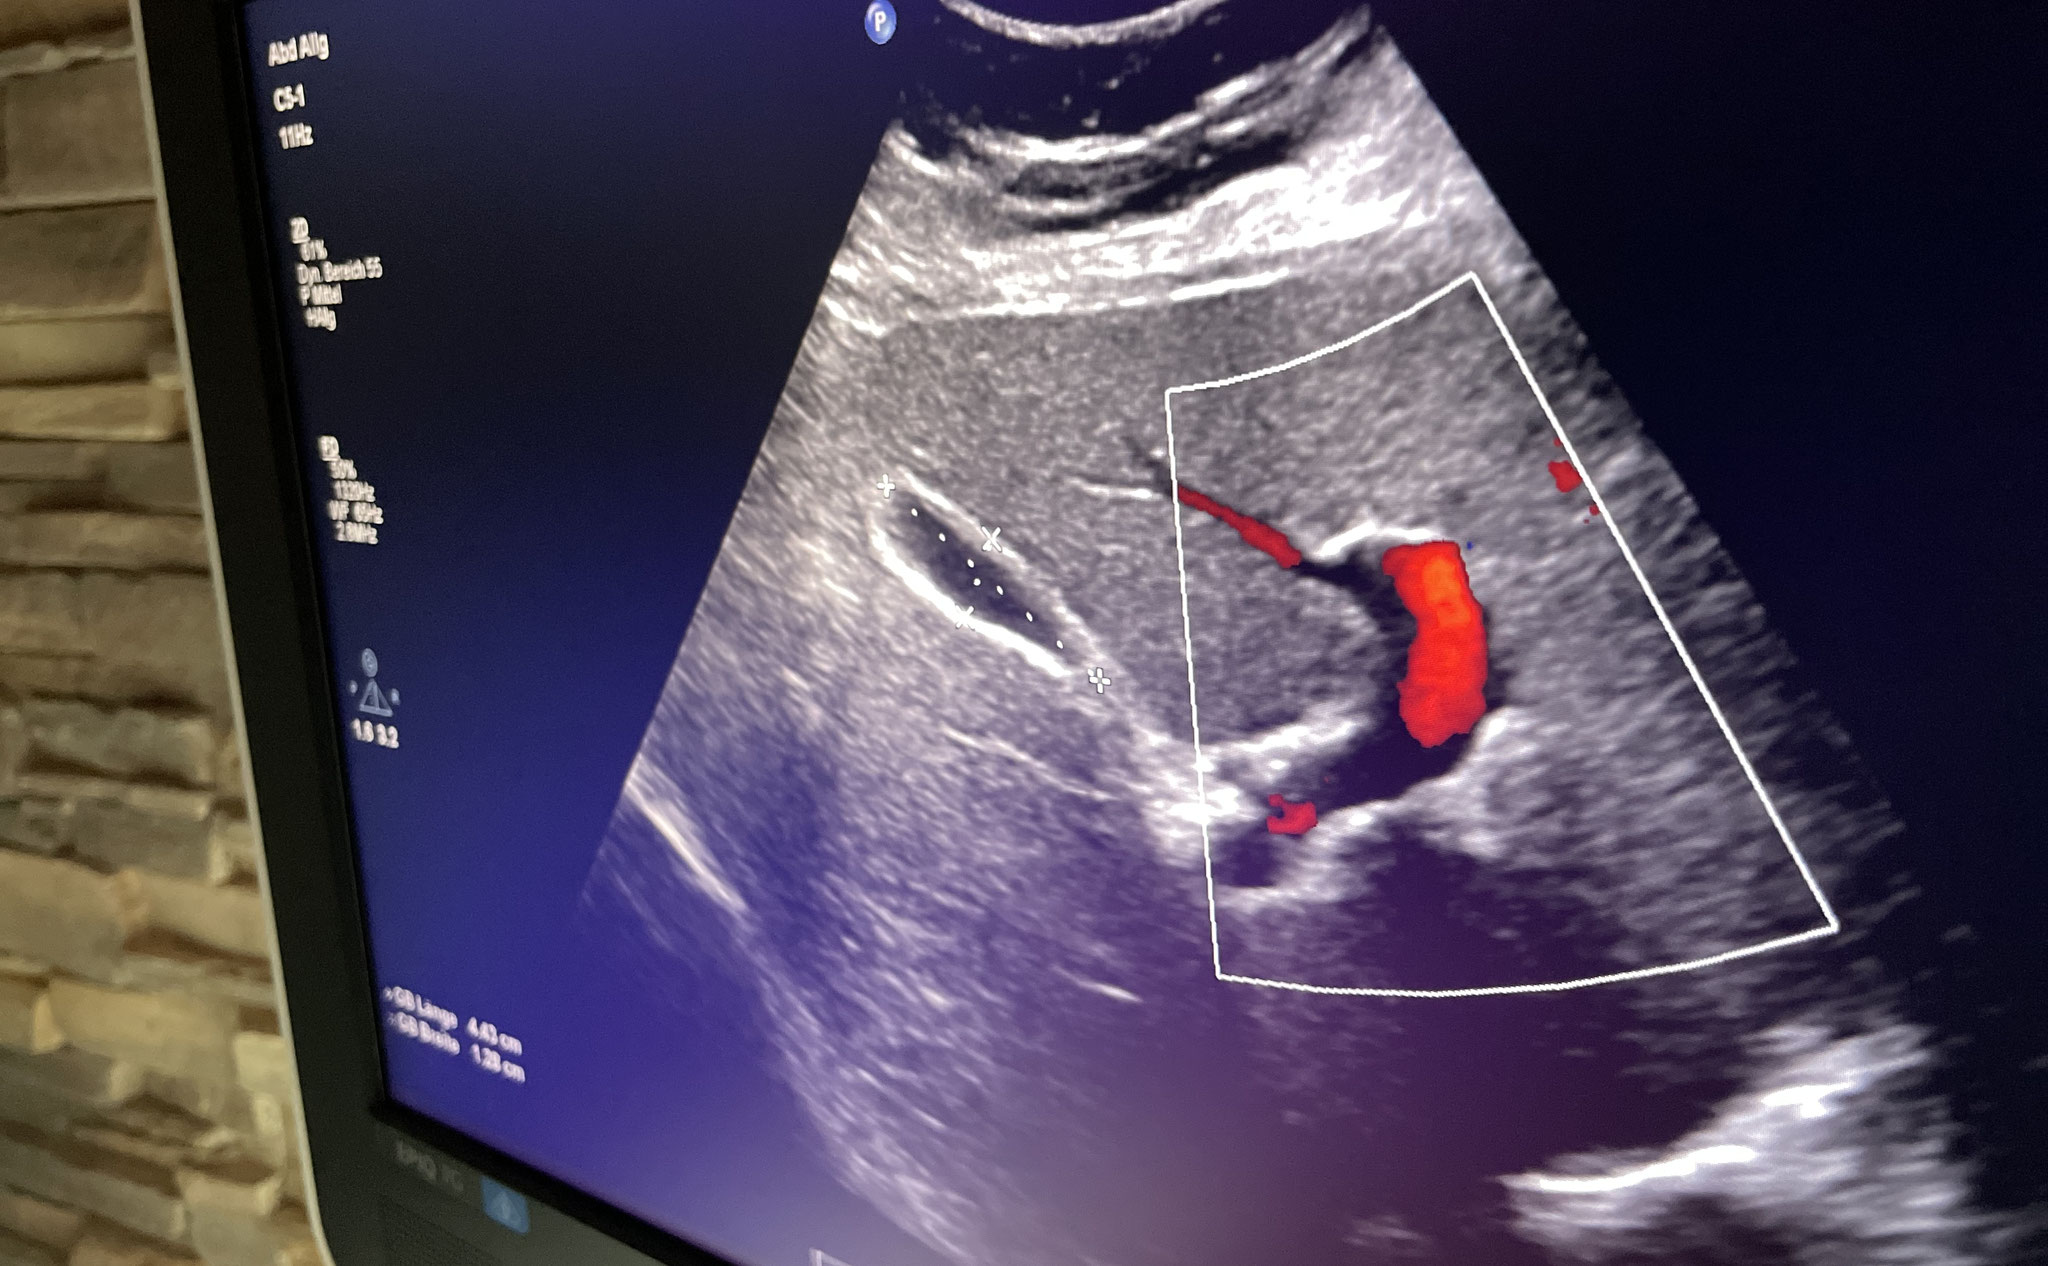

Duplex-Sonographie

Halsgefäße / Abdomen / Schilddrüse